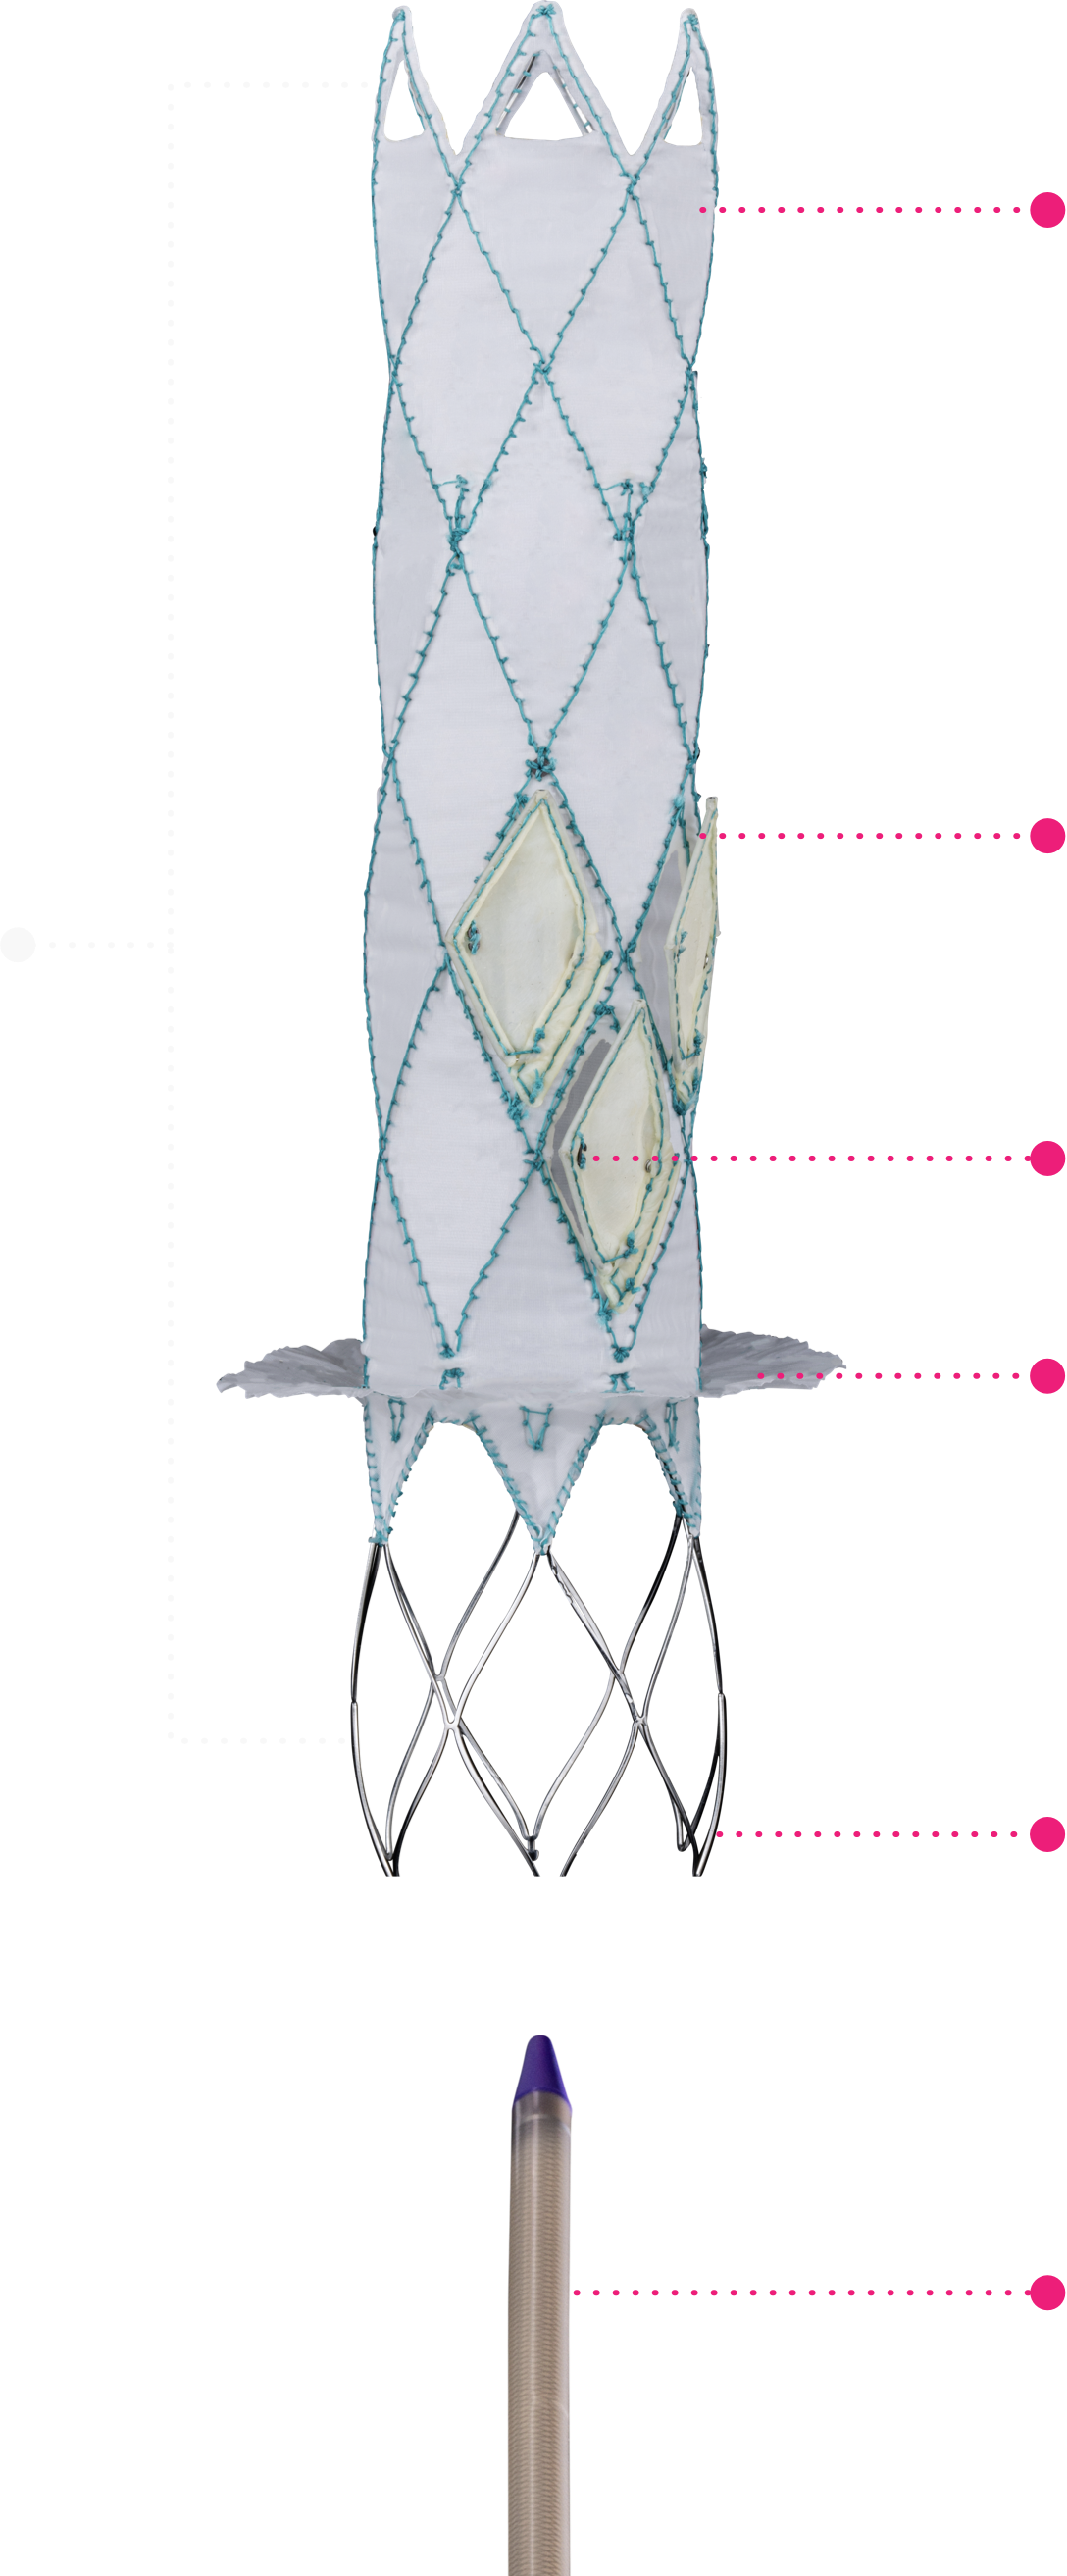

Technical Excellence for Comprehensive Care

Trillium™ is meticulously crafted for the unique demands of the tricuspid valve environment.

This stent graft, featuring a valved wall, is designed to span the right atrium with secure fixation

in the Superior Vena Cava (SVC) and Inferior Vena Cava (IVC), leaving the native valve untouched.

Migration Resistant

A single device anchored to two

apposing anatomies (SVC & IVC),

provides reliable anchoring and full

migration resistance.

Multiple, Normally Open Valves

Provide extremely low filling

(diastolic) pressures, with an

increased closing volume for the

benefit of patients with RV failure.

Large Flange Sealing Skirt

Creates a secure seal that fits a wide

range of anatomies, while allowing

the necessary hepatic vein inflow.

Mechanically Durable

Designed for long-term fatigue

resistance. Durable for decades of

cardiac function.

Radio-Opaque Markers

Ensure precise positioning under a

strictly fluoroscopic procedure.

Atraumatic Stent Ends

Provides reliable anchoring,

reducing the risk of complications

during and after the procedure.

Low Profile Delivery System

24 Fr delivery system for

venous transfemoral approach.